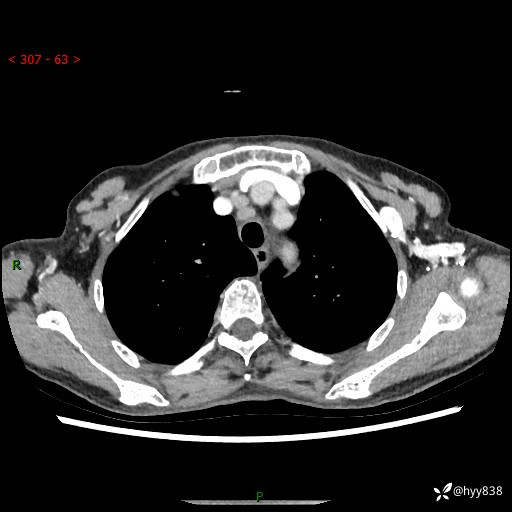

胸部CT平扫+增强